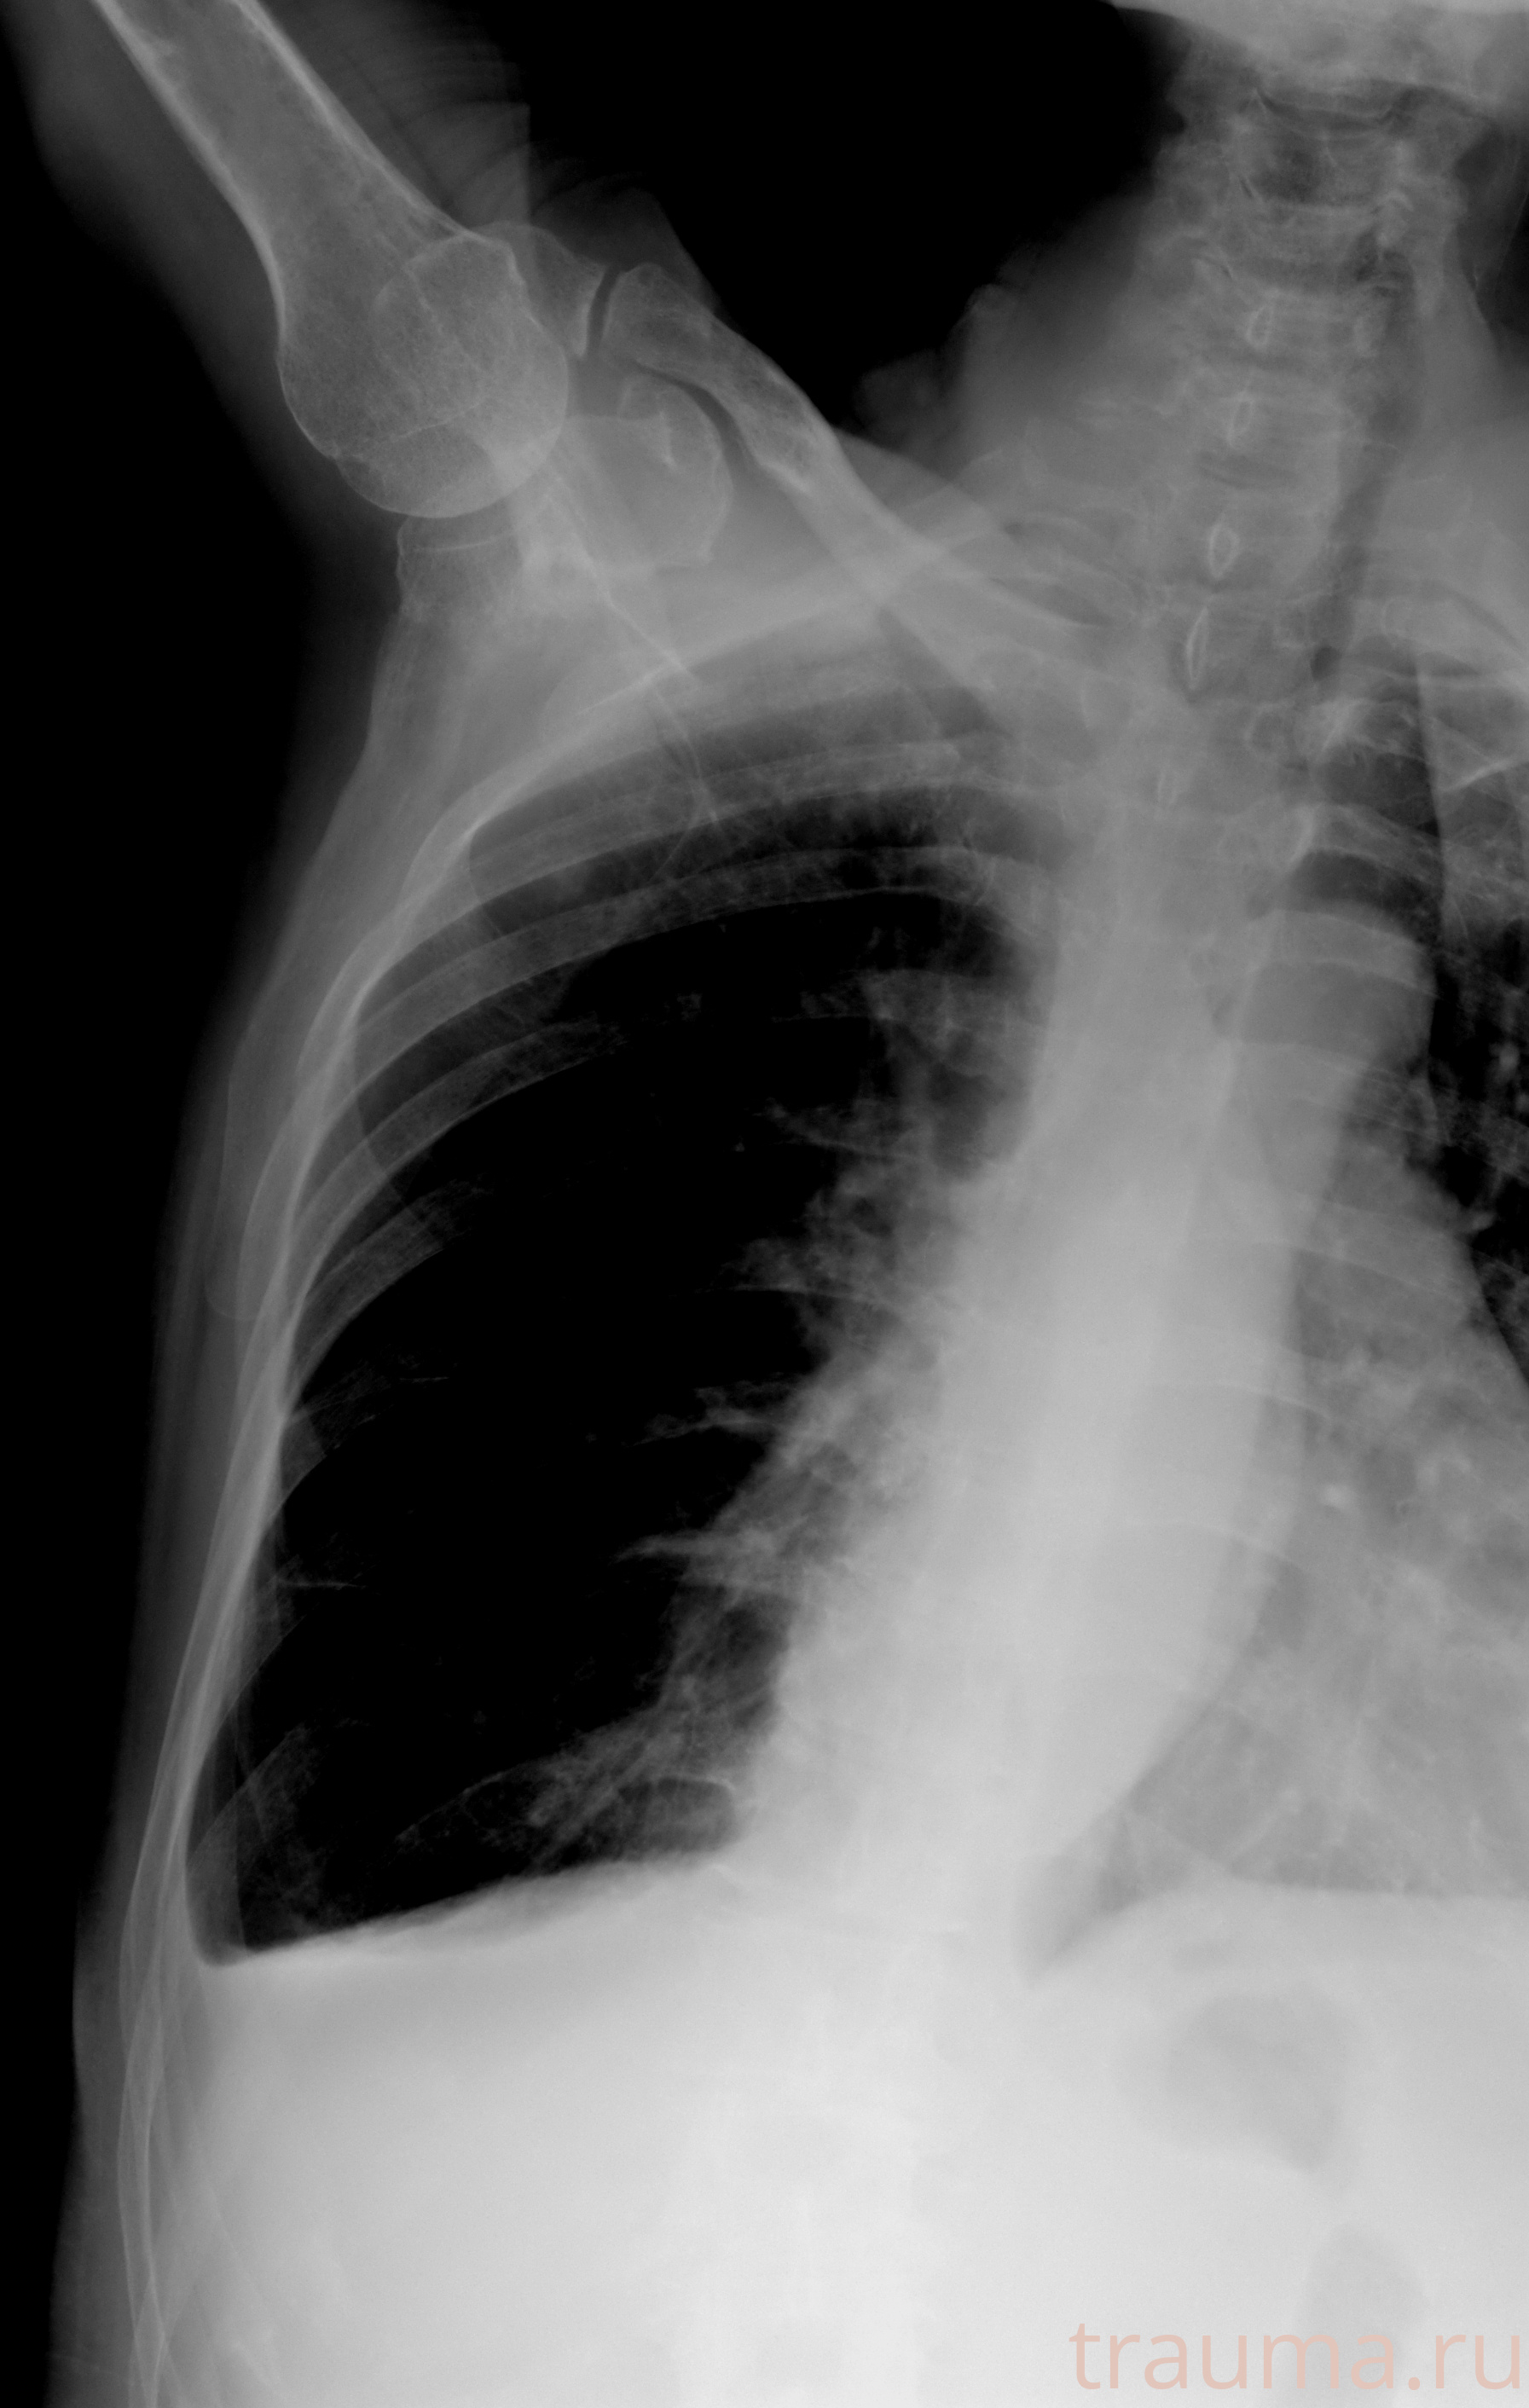

Рентгенограммы

Натуживание 26.12.2025 21:16:34

Рентген на дому: по вашему адресу приезжает врач-рентгенолог, травматолог-ортопед с мобильным рентгеновским аппаратом, проводит диагностику травмы или заболевания, делает необходимые рентгенограммы, дает рекомендации по дальнейшему лечению. Получить качественные снимки в домашних условиях возможно благодаря уникальной методике, разработанной МосРентген Центром для института  Склифосовского